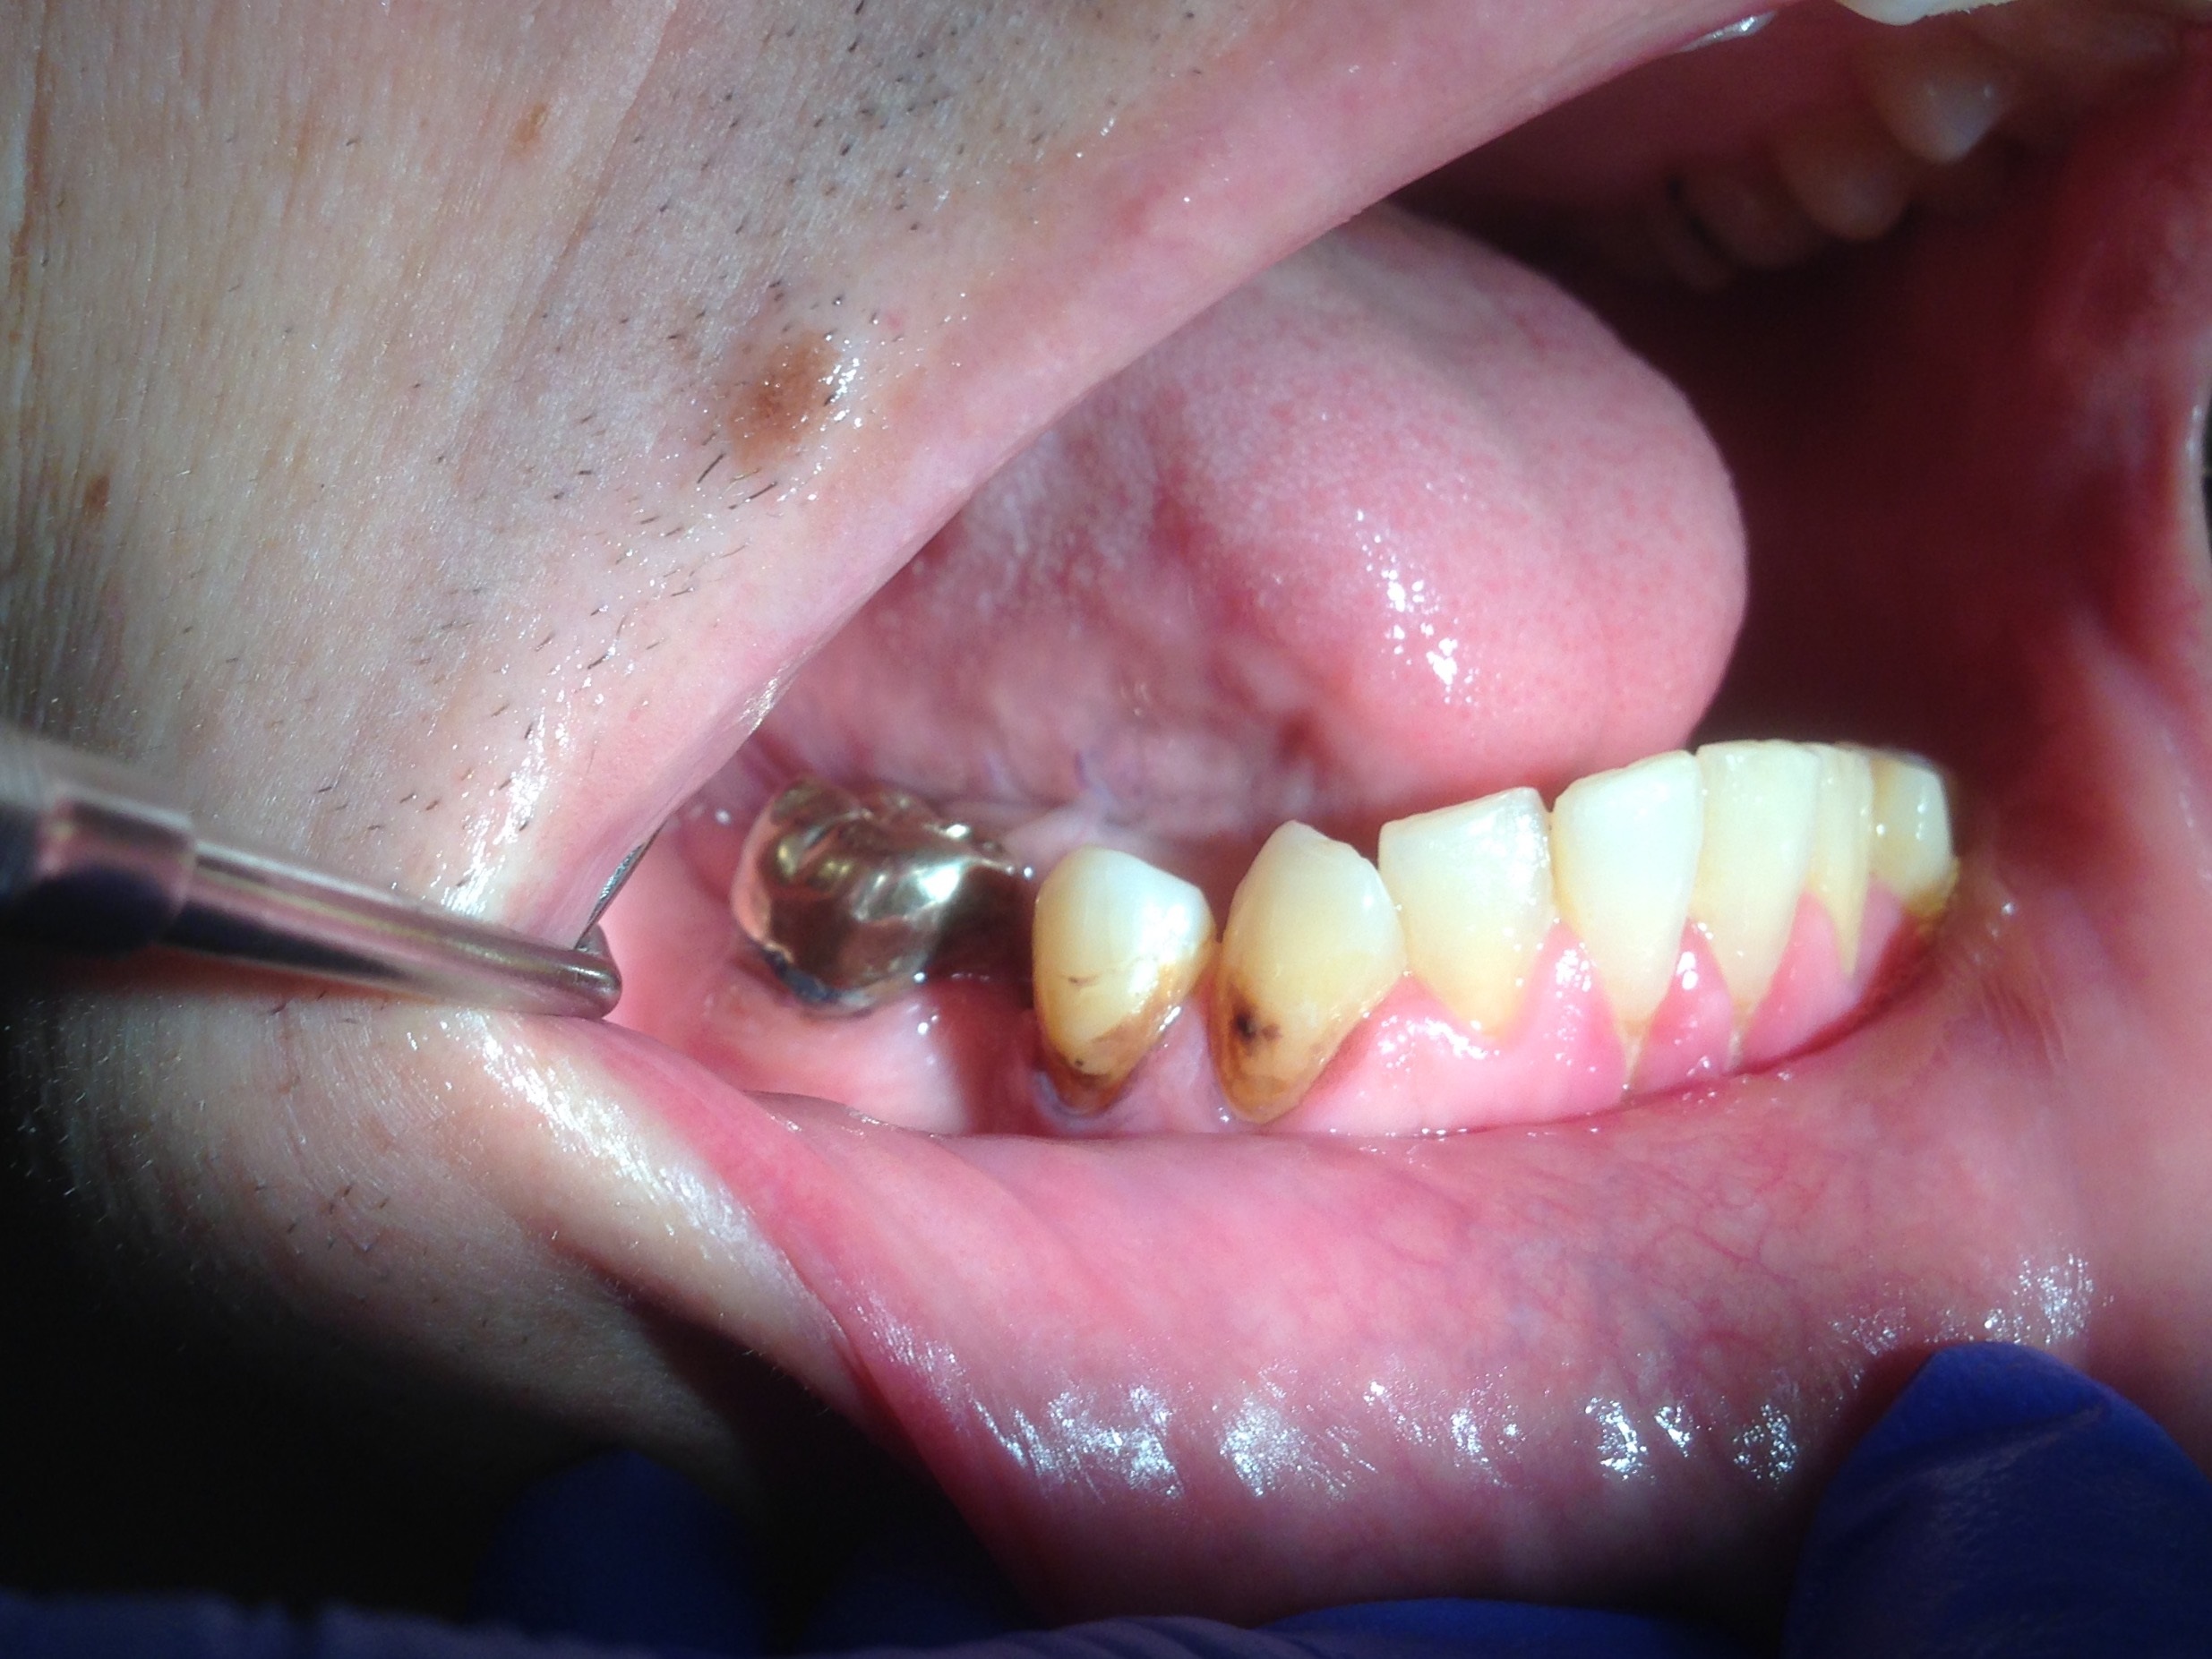

Fig 11. Note demineralization of smooth surfaces, carious lesions at the gingival margins, and associated inflammation of the periodontium.

Figure 11